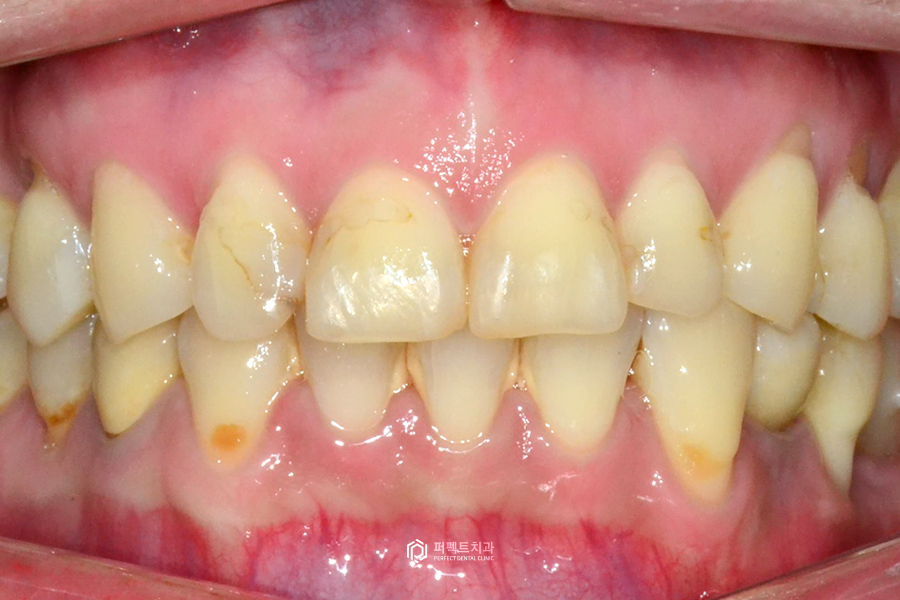

초진사진

처음 내원하셨을 때 사진을 보시면 레진으로 때웠던 부분이 시간이 지나면서 변색이 되어 얼룩덜룩 해진 것을 볼 수 있습니다. 레진으로 넓은 부분을 때우게 되면 몇 개월만 지나도 변색이 생길 수 있어 사진으로 보시는 것처럼 깔끔하지 못하게 보일 수 있습니다.

레진으로 인한 변색 뿐만아니라 치아 사이사이 마모되어 있는 부분들과 아랫니 사이 치석이 있는 것을 확인할 수 있습니다.

그리고 앞니 치아형태를 확인해보시면 앞서 말씀드린 것처럼 밑으로 내려오면서 퍼지는 삼각형 모양의 치아인 것을 확인할 수 있습니다. 이런 부분을 가지런하게 일자로 내려오는 형태로 바꾸길 원하셨습니다.

송곳니에서 송곳니까지 6개의 치아가 있는데 환자분의 경우 아래 치아 하나가 결손되어 5개밖에 없으셔서 윗니 6개, 아랫니 5개를 진행하였습니다.